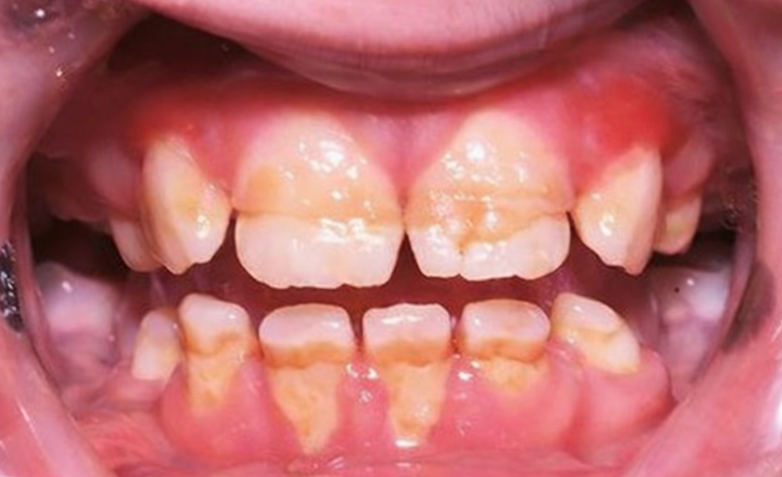

그러나 아이들은 단 음식을 좋아하고

양치 습관이 아직 서툴러 충치가

쉽게 발생합니다.

충치는 초기에는 치아 표면에만 머물지만,

점차 깊어져 치수까지 도달할 수 있습니다.

법랑질 저형성증(Enamel Hypoplasia)

영구치 변색이나 형성 이상이 생기기도 합니다.